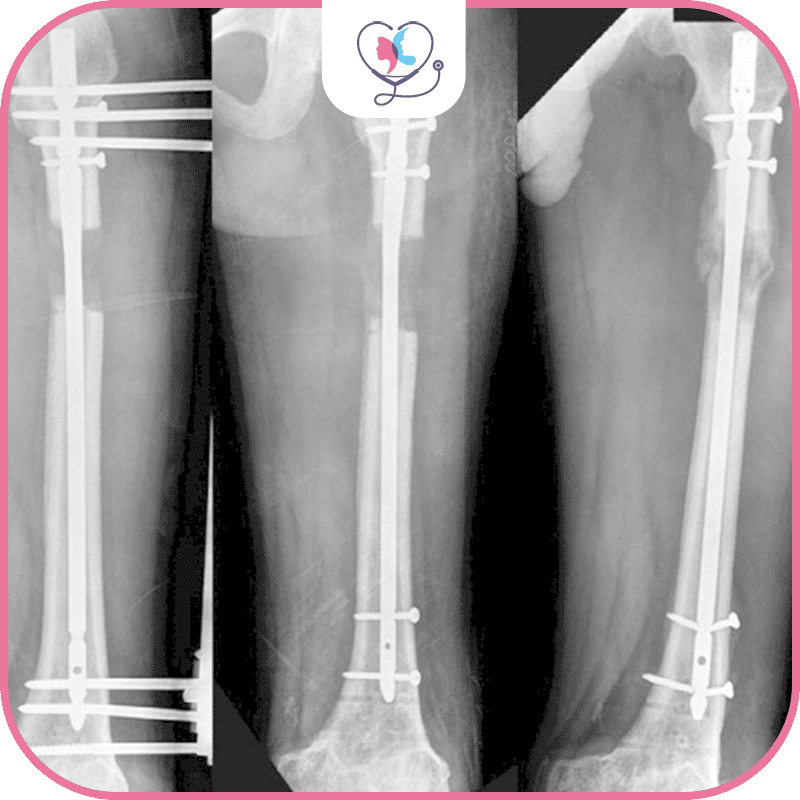

طريقة LON هي اختصار لـ lengthening over nails وهي تقنية حديثة نسبياً تستخدم لزيادة الطول، تجمع بين تقنيات التثبيت الخارجي والمسمار النخاعي في عملية تطويل القامة، وتُعرف هذه الطريقة أيضاً باسم المثبت الخارجي، أو الطريقة المدمجة لأنها تتضمن استخدام كل من المسامير داخل النخاع والمثبتات الخارجية.

يتمُّ فيها تثبيت جهاز خارجي تقني يُعرف بـ "جهاز التمدد" أو "جهاز لون"، وهو جهاز يتيح للعظم التمدد تدريجياً على مر الوقت، ويُستخدم هذا الجهاز لتحفيز نمو العظم وزيادة طوله جنباً إلى جنب مع المسمار النخاعي وهو الجزء الداخلي المسؤول عن التثبيت ويعتمد اختيار الجهاز الخارجي بشكل أساسي على تفضيلات الجراح الذي يقوم بإجراء عملية تطويل القامة.

في هذه العملية، يثبّتُ المسمار النخاعي، وهو عبارة عن مسمار معدني، جراحياً داخل تجويف العظام مما يساعد على تمديد العظام ببطء وتحفيز نمو العظام الجديدة، وهذه التقنية تجمع بين فوائد التثبيت الخارجي والمسمار النخاعي، مما يساعد في تحسين نتائج عملية تطويل القامة، كما أنها تقنية موثوقة للغاية وأكثرها شيوعاً في العالم لأنها الأنسب لاستقرار العظام.

- تعتمد التقنية استخدام المسمار داخل النخاع كتثبيت داخلي وهو مصنوع من سبائك التيتانيوم.

- يقرر الطبيب حجم الظفر من خلال مراجعة صور الأشعة السينية "8,5 ملم، 10,7 ملم، 11,5 ملم أو 12,5 ملم" أثناء العملية.

- يتُّم إدخالها جراحياً في تجويف العظام، وبما أن الظفر متوافق حيوياً، فهو لا يحتوي على أي عناصر من شأنها أن تسبب ضرراً للجسم.

- يثبّت المسمار بمسامير من أجل الحفاظ على الطول الذي تم تحقيقه، وبعد ذلك، تتم إزالة المثبت الخارجي.

- يمكن إزالة المسامير داخل النخاع بناءً على طلبك بعد اكتمال عملية تثبيت العظام بالكامل.

- وقد يستغرق الأمر سنة أو سنة ونصف للتخلص من الظفر بإجراء قصير، ومع ذلك، فإن البعض يفضلون عدم إزالته.